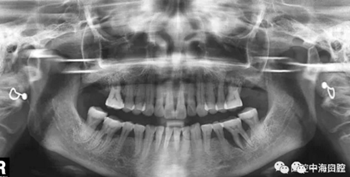

由于智齒的生長位置特殊,導(dǎo)致了拔除難易不同,如智齒出現(xiàn)橫著長或者靠近牙神經(jīng)的話,則難度會較高,一般人只需拍個口腔全景片,但相對于智齒靠近神經(jīng)管的情況,還可能需要拍CT,這都很考驗牙醫(yī)的技術(shù)。

拔牙非小事,請不要拿成本衡量牙醫(yī)的價值!

下面這兩張圖,據(jù)說拔牙費時1.5小時,收費14000元。